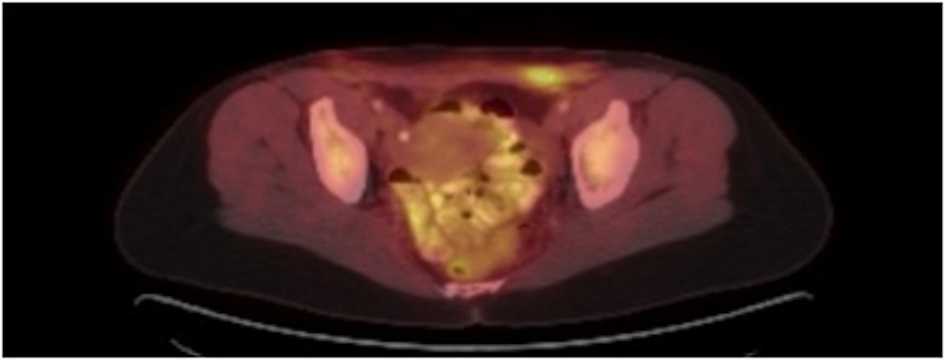

The patient initially underwent resection of the mass and given that a sarcoma was suspected, her wound was left open while tumor margins were obtained. The posterior tumor margin returned positive at three millimeters and a reexcision with subsequent wound closer was performed. The initial biopsy report suggested Ewing’s sarcoma/Primitive Neuroectodermal Tumor with findings concerning for melanoma. A EWSR-1 gene rearrangement and BRAF V600E mutation were then sent to confirm ES/PNET and melanoma respectively. A PET-CT revealed hypermetabolic activity with soft tissue stranding in the subcutaneous region of the anterior pelvis, bilateral pelvic and inguinal hypermetabolic lymph nodes, and a four-millimeter left apical lung nodule (Fig. 2, 3). These findings were concerning for a metabolically active neoplasm.

![]() Click for large image | Figure 2. Pelvic CT with abdominal wall soft tissue stranding after tumor resection. |

![]() Click for large image | Figure 3. PET CT with hypermetabolic activity with abdominal wall soft tissue stranding and pelvic/inguinal hypermetabolic lymphadenopathy. |